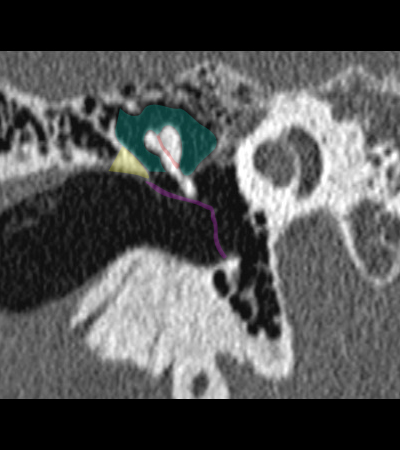

Radioanatomie du rocher sur coupes TDM

Différentes coupes de référence (A. Attyé 2013)

Coupe axiale passant par le canal semi-circulaire supérieur Coupe axiale passant par le canal semi-circulaire latéral Coupe axiale passant par le modiolus de la cochlée Coupe axiale passant par la fenêtre ronde Coupe axiale passant par le ganglion géniculé Coupe axiale passant par l'articulation incudo-malléaire Coupe axiale passant par la partie pétreuse de l'artère carotide interne Coupe axiale passant par le nerf tympanique

Coupe axiale passant par le foramen styloïde Coupe coronale passant par le muscle tenseur du tympan Coupe coronale passant par le recessus epitympanique Coupe sagittale passant par le segment mastoïdien du nerf facial coupe sagitalle oblique passant par le canal semi-circulaire supérieur (plan de Pöschl) Reconstruction axiale passant par le plan de l'étrier Coupe axiale passant par les apex pétreux